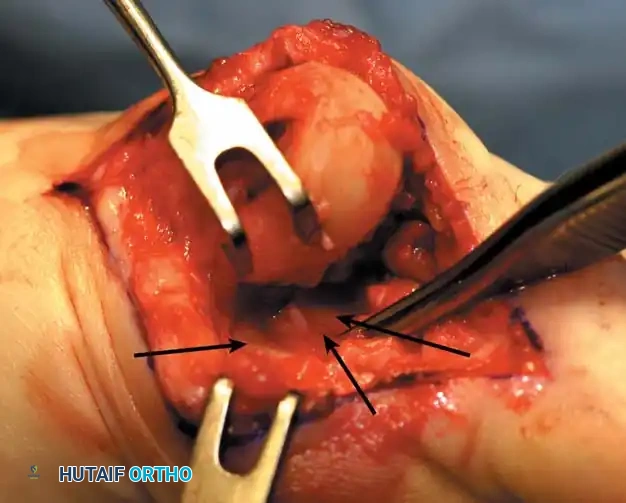

• Using a Freer elevator or a small osteotome for its strength, mobilize the fi bular sesamoid (Fig. 78-31A to C). This may be diffi cult in elderly patients with signifi cant deformity and adherence of the sesamoid to the metatarsal head. Lift the metatarsal dorsally for exposure (Fig. 78-31D and E).

Fig. 78-31 Excision of fi bular sesamoid in modifi ed Keller procedure. With base of proximal phalanx removed and medial eminence excision, exposure of fi bular sesamoid is not as diffi cult from medial incision. A, Operative photograph showing elevation of fi rst metatarsal with strong two-tooth retractor and use of small osteotome to mobilize fi bular sesamoid and lateral capsuloligamentous (frequently contracted) structures. Osteotome is between metatarsal head and lateral sesamoid. When mobilization of fi bular sesamoid is complete, entire sesamoid is visible for excision. Note chondromalacia of tibial sesamoid articular surface medial to osteotome. B, Fibular sesamoid has been excised, and lateral capsular structures and conjoined tendon (in forceps) have been released. Neurovascular bundle to lateral side of hallux is adjacent to these structures. C, Diagrammatic representation of modifi ed Keller procedure. By excising fi bular sesamoid, valgus moment of conjoined tendon of fl exor hallucis brevis and adductor hallucis no longer pulls fl exor hallucis longus tendon laterally (carrying hallux with it) through capsulosesamoid plantar plate and pulley system. D, Metatarsal head must be lifted dorsally to excise fi bular sesamoid under direct vision. E, Note exposure of fi bular sesamoid after mobilization of metatarsal head. Continued